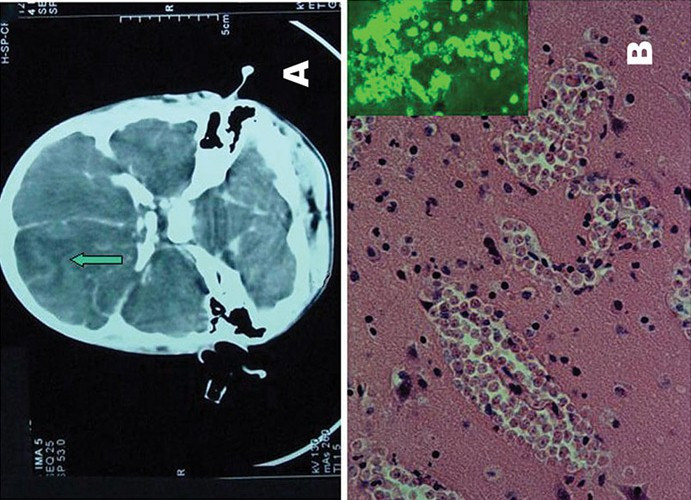

| “Amip ăn não người” hay còn gọi là bệnh viêm não-màng não do đơn bào Naegleria fowleri gây ra, đây là một bệnh rất hiếm gặp, nhưng có tỷ lệ tử vong rất cao lên đến 98%. |

| Khẳng định Amip Nagleria fowleri chỉ xâm nhập qua niêm mạc mũi, Tiến sĩ Trần Phủ Mạnh Siêu, Giám đốc Trung tâm Y tế Dự phòng TP HCM khuyên người dân không nên lo nhiễm ký sinh trùng này khi ăn rau hoặc tắm hồ bơi. |